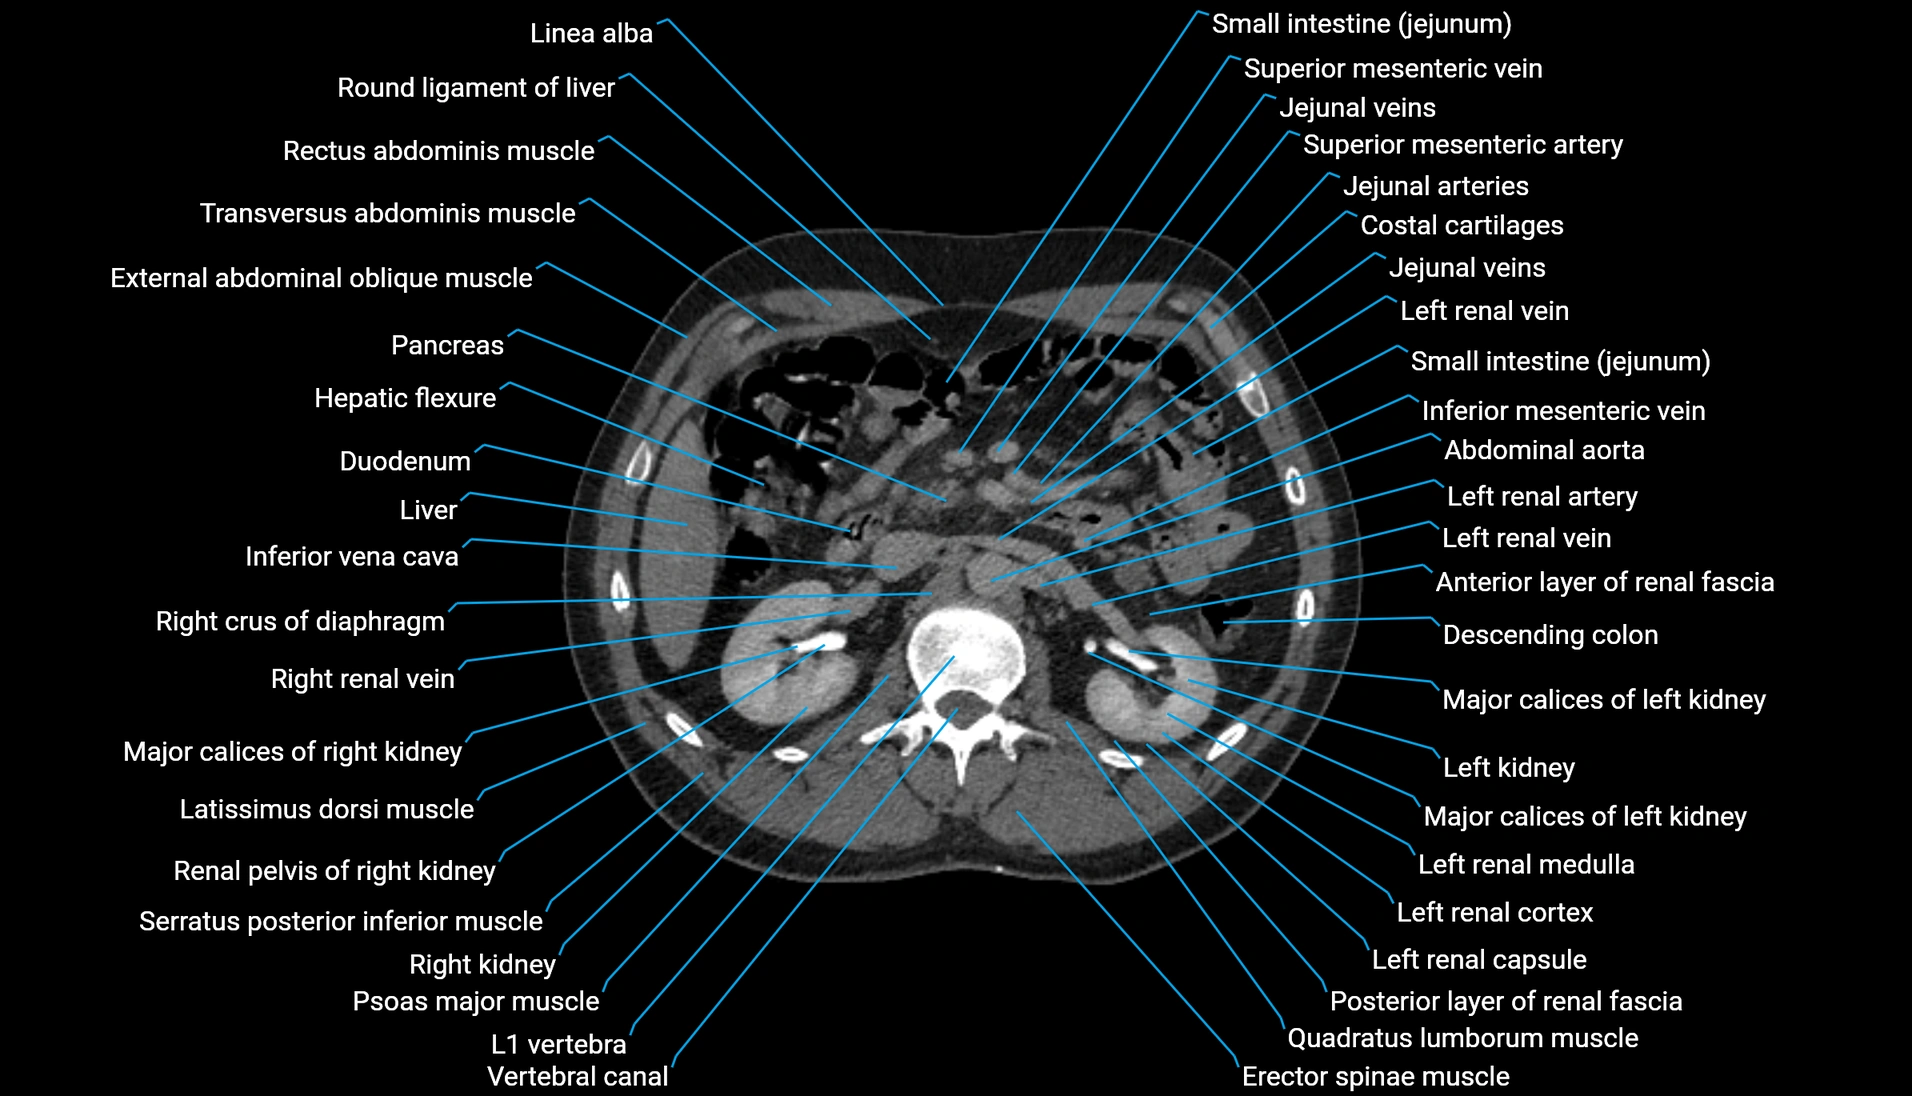

CT Appearance

Non-contrast CT:

-

Demonstrates cortical bone of acetabular rim in excellent detail

Detects fractures, dysplasia, retroversion, or bony overcoverage (pincer impingement)

3D reconstructions used in preoperative hip surgery planning

CT VRT 3D image

CT image